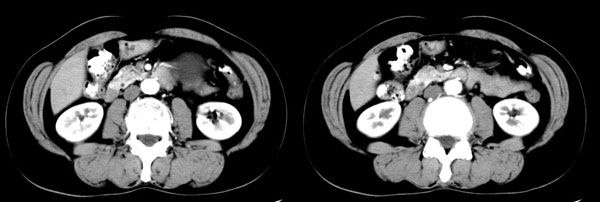

女性,58岁。卵巢癌术后4年余,无不适。体检b超发现左上腹肿块。

ct平扫加增强扫描:胆囊折叠,壁厚,其内见结石。胰腺体尾部见一5.8x7.5cm囊性肿物,ct值12hu,壁薄,增强扫描未明显强化,胰头不大,强化均匀。